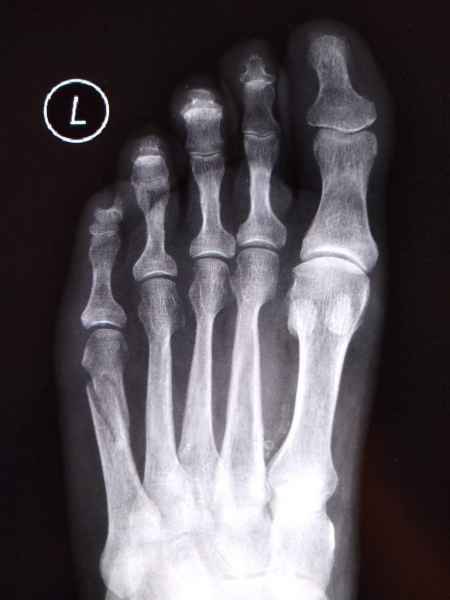

El pie es el órgano distintivo y característico de la especie humana, la única criatura que marcha erguida. El pie es una muy compleja estructura de arquitectura perfecta, adaptado a su función de apoyo, traslación, salto, con una riquísima sensibilidad que le permite detectar las más leves imperfecciones del suelo para estabilizar la marcha.

Tanto la estructura del pie como su funcionalismo que es la marcha, pueden ser asiento y manifestación respectivamente de alteraciones locales ó sistémicas, por lo que su cuidadoso examen resulta de extrema utilidad diagnóstica.